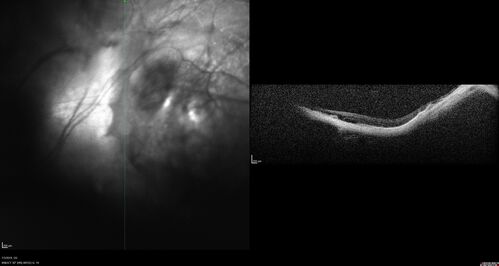

Staphyloma and Atrophy with Vitreoretinal traction

Only eye of patient with Albinism and decreasing vision now 5/200 in this 72 year old man.  There is myopic tractional maculopathy.  The patient also has albinism by history.